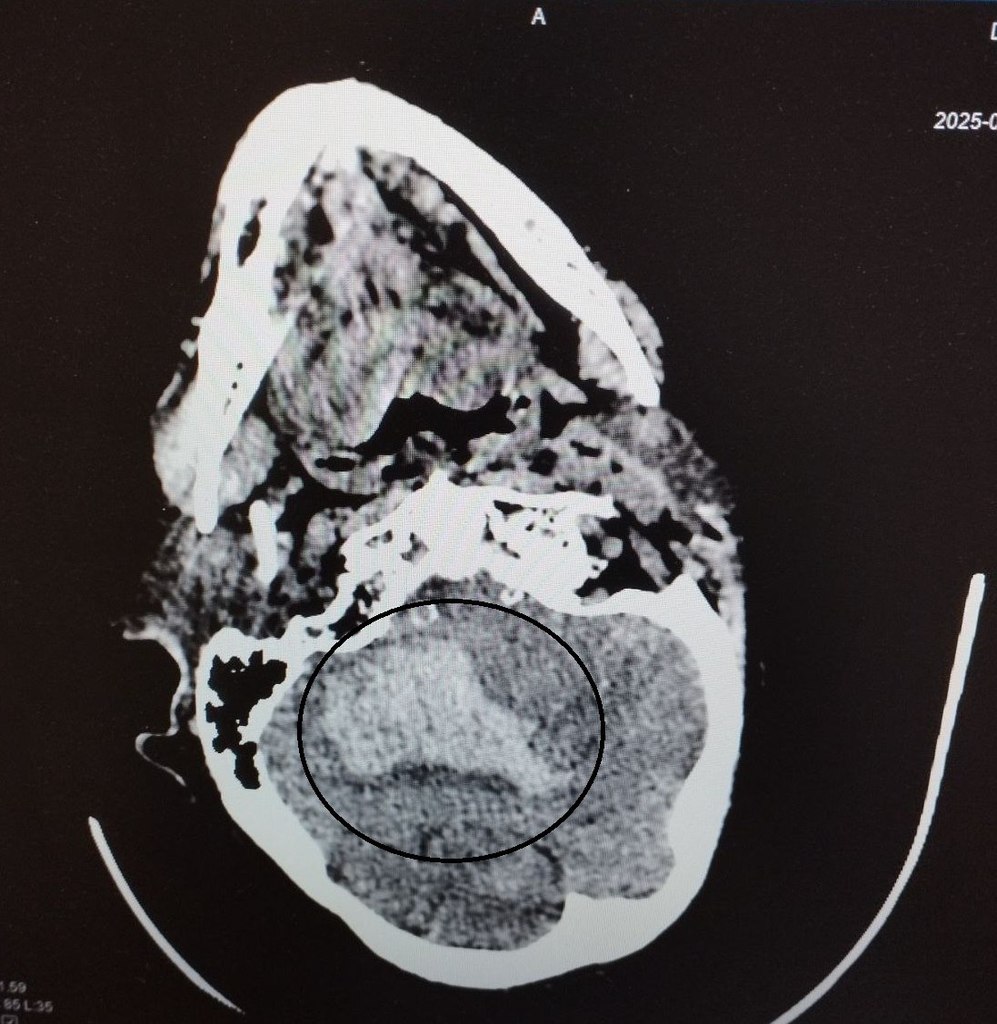

Обследовав женщину, врачи поставили диагноз – геморрагический инсульт правого полушария мозжечка, сопровождающийся внутримозговой гематомой, прорывом крови в желудочковую систему и кровоизлиянием.

На фото – томогораммы, на которых видны внутримозговые гематомы в области правого полушария мозжечка, в стволе головного мозга, кровоизлияния в желудочковую систему мозга.